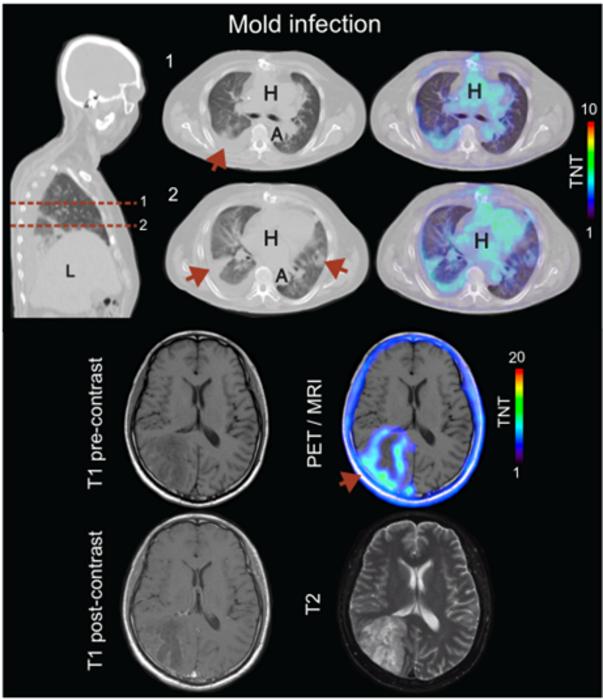

Figure 1. Representative 18F-FDS PET/CT and PET/MRI images of patients with pulmonary (n = 3) and cerebral (n = 2) invasive mold infections.

18F-FDS was found to quickly and specifically accumulate inside a wide range of disease-causing molds (including drug-resistant strains) while showing no uptake in heat-killed molds or human cells. Among mice, it accurately identified fungal infections in the lungs, brain, and sinuses, and was able to distinguish these from non-infectious inflammation. In patient studies, 18F-FDS PET safely detected and localized mold infections—including one missed by a previous brain MRI.